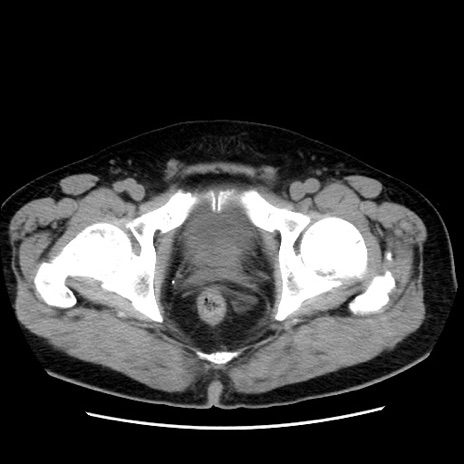

症例16(横断像)

【症例】 70歳代男性

【主訴】 腹痛、嘔吐

【現病歴】 約1ヶ月前より間欠的に腹痛と嘔吐あり、当院消化器内科を受診したところCTで多発する肝臓のLDAを指摘され、精査中であった。以降は消化器症状は安定していたが、2日前より嘔気と腹痛があり、同日より排便・排ガスが消失した。改善認めず、 本日、救急外来を受診した。

【既往歴】 大腸ポリープ切除後。

【身体所見】意識清明・会話良好、BT 36.3℃、BP 127/80mmHg、 P 80bpm、腹部:膨満あり、平坦・軟、上腹部正中および下腹部正中に圧痛あり、反跳痛なし、筋性防御なし。

【データ】WBC 7200、CRP 0.77